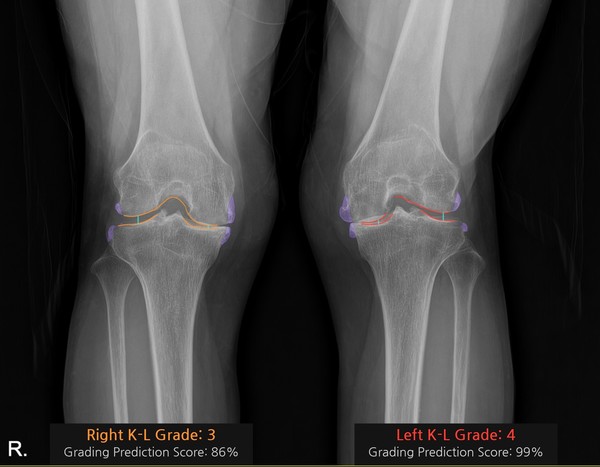

'코네보 코아(CONNEVO KOA)'는 무릎 X-ray 영상을 분석해 관절염 심각도를 ’K-L(Kellgren–Lawrence) 등급’으로 판정하고, 골극과 관절 간격을 시각화해 제공한다. 이를 통해 진단의 일관성을 높이고 환자와 상담 시 유용한 시각자료로 활용할 수 있다.

공동 연구자인 중앙대병원 정형외과 김성환 교수는 “AI 솔루션이 관절염 상태를 직관적으로 보여줘 환자 이해도가 크게 향상됐다”며 “실제 사용 경험에서도 만족도가 매우 높다”고 말했다.